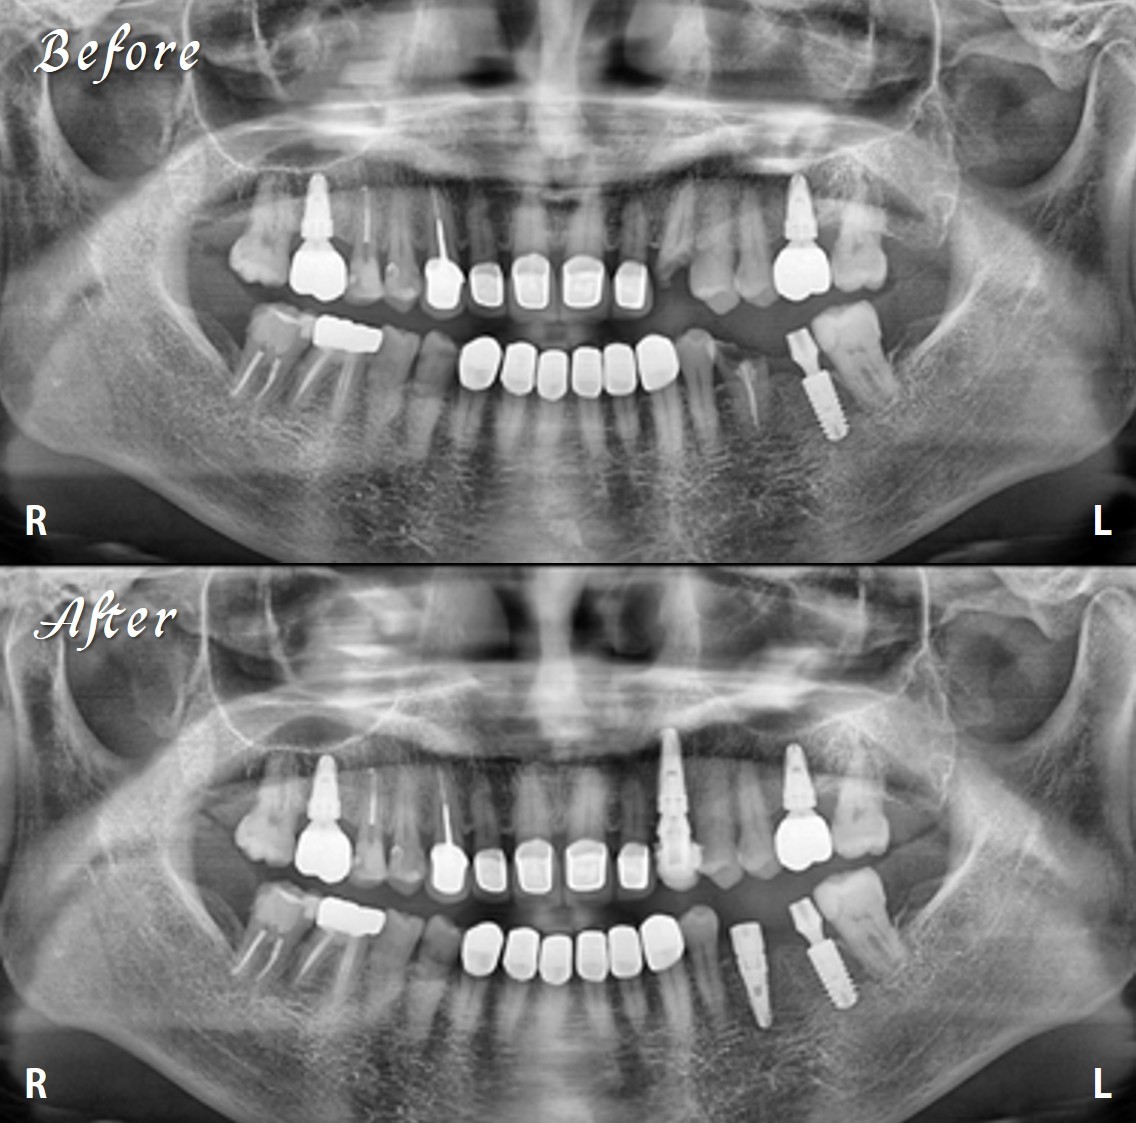

一位女牙醫師急忙跑來找陳博士,植了兩顆牙後,因為時間太趕,術後X光都來不及拍,急急忙忙又趕回去上班。

過了幾天,她特地抽空回來補拍X光,看到影像滿意的笑容再度浮現。

別人的植牙講求快速,陳俊龍博士整套的Leon’s concept精奈創一鑽植牙,講的是高效與精準。

不是追求速度,而是整合技術、設計與經驗,一次到位,穩定可靠。快,只是表現;高效,才是實力。